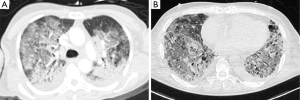

The most common CT finding in ARDS is the presence of large infiltrates and loss of aeration especially in the dorsal dependent regions (Figure 2). Compared to CXR, CT allows a more precise assessment of the morphology and distribution of the lesions, nonetheless ARDS has a broad spectrum of radiological manifestations, therefore differential diagnosis with other lung conditions can still be complex. In the late phase, CT detects precisely the possible evolution of lung damage: patients who survived after severe ARDS can show a honeycomb-like pattern, indicating an irreversible fibrosis with restrictive syndrome. Concerning ARDS ventilatory management, CT can be useful to assess the degree of recruitment potential, namely the responsiveness to higher PEEP levels (19), the concept of ventilation titration based on imaging has been then proposed (20). Several studies assessed the responsiveness to recruiting by performing two or more CT scans during breath-hold at different PEEP levels, e.g., 5 vs. 45 cmH2O (19,21). However, it has still to be demonstrated that setting PEEP according to imaging can improve the clinical outcome.